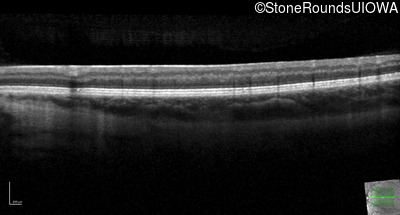

Optical Coherence Tomography - Left - 20/200 +2

Exemplar / OCT Stack

OCT Stack